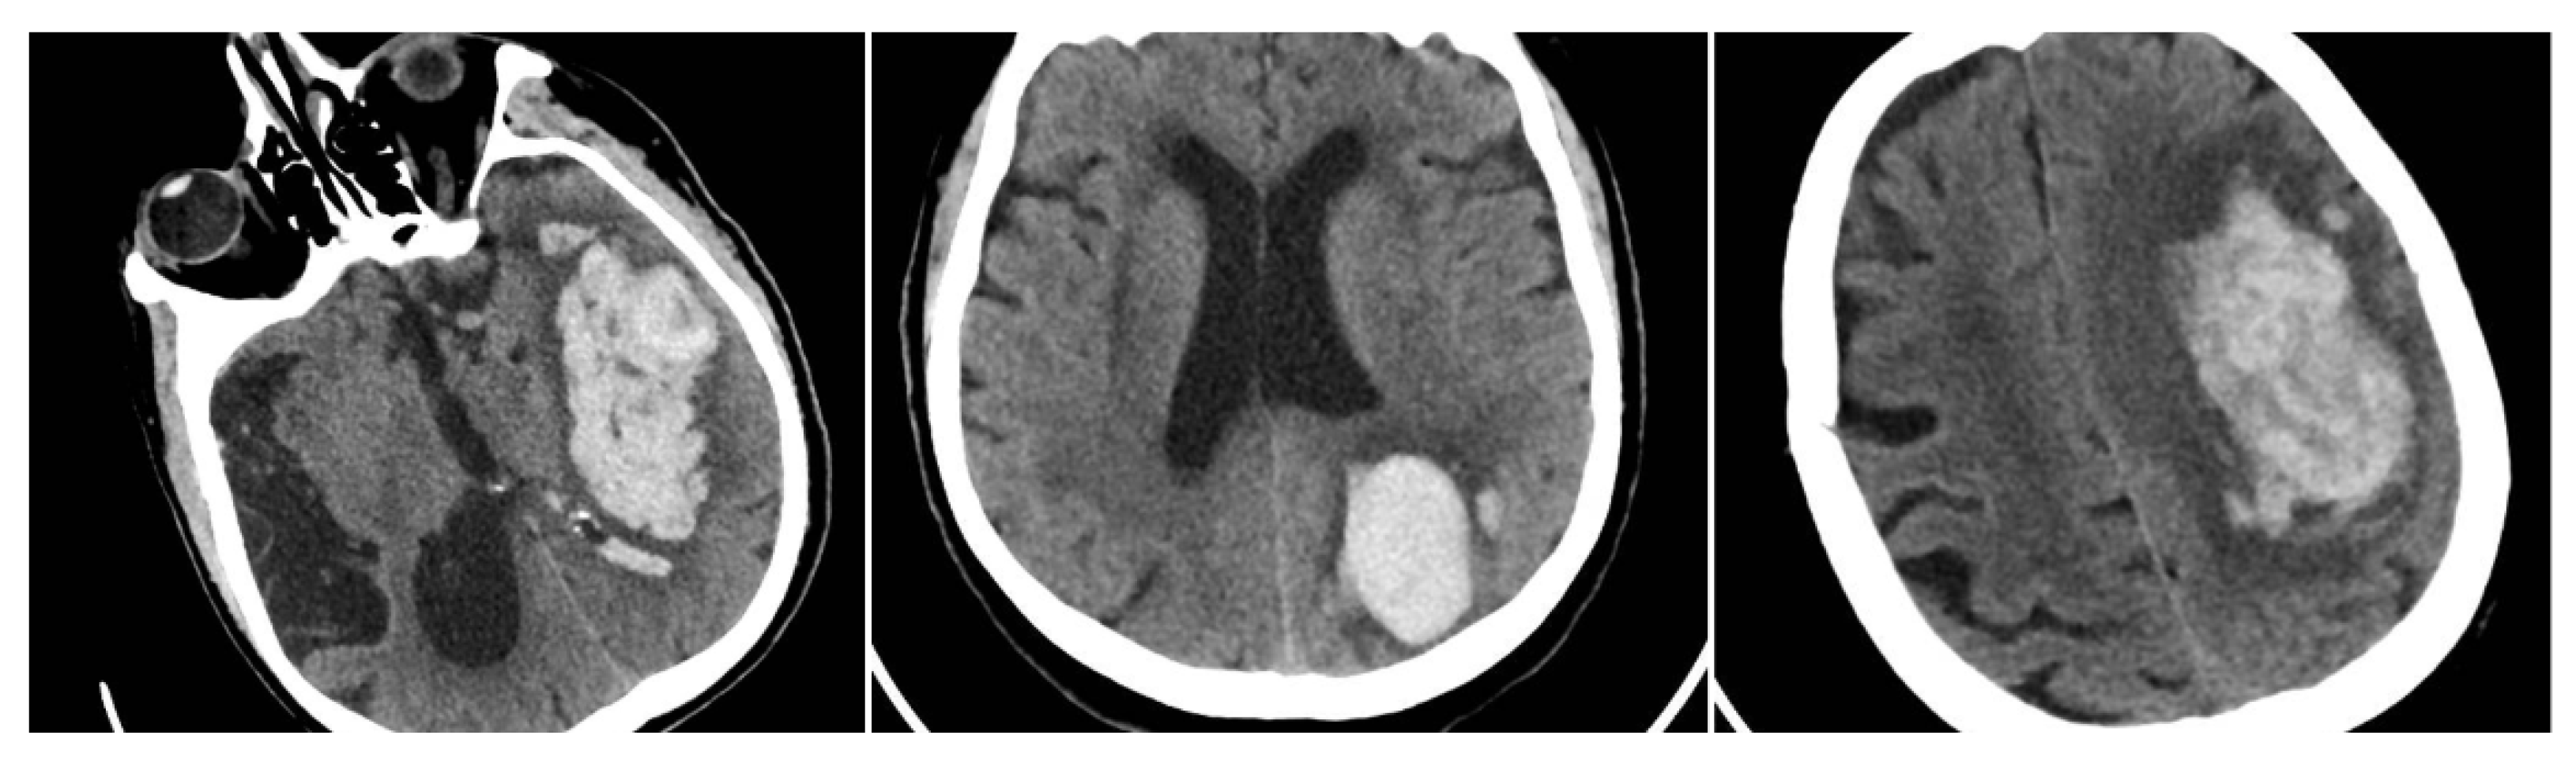

The Blend Sign (BS) was recorded when a well-defined hypoattenuating region directly abutted a hyperattenuating area within the same hematoma, differing by ≥18 HU, without the hypodense portion being fully encapsulated by the hyperdense region (BS = 1 if present, otherwise 0) (Figure 1) [9].

Figure 1. (Left) Hematoma showing Black Hole and Blend Signs; (middle and right) other examples of Blend Signs.

The Black Hole Sign (BHS) refers to a discrete, well-defined hypoattenuating region fully enclosed within a hyperdense clot with ≥28 HU difference and no continuity with normal parenchyma (BHS = 1 if present, otherwise 0) (Figure 2) [10].